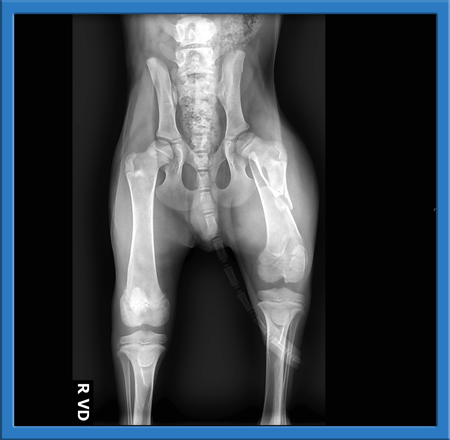

We decided to take Buster into our rescue and get him the vet care that he needed. Buster arrived yesterday and went straight to Alicia Pet Care Center and saw Dr. Wheaton. Unfortunatley, what we were hoping was a hurt paw turned out to be a fractured Femur. You can see from the xrays that this little guys large bone in his leg is broken almost in half. We do not know how long he suffered like this, but know that he must have been in considerable pain.